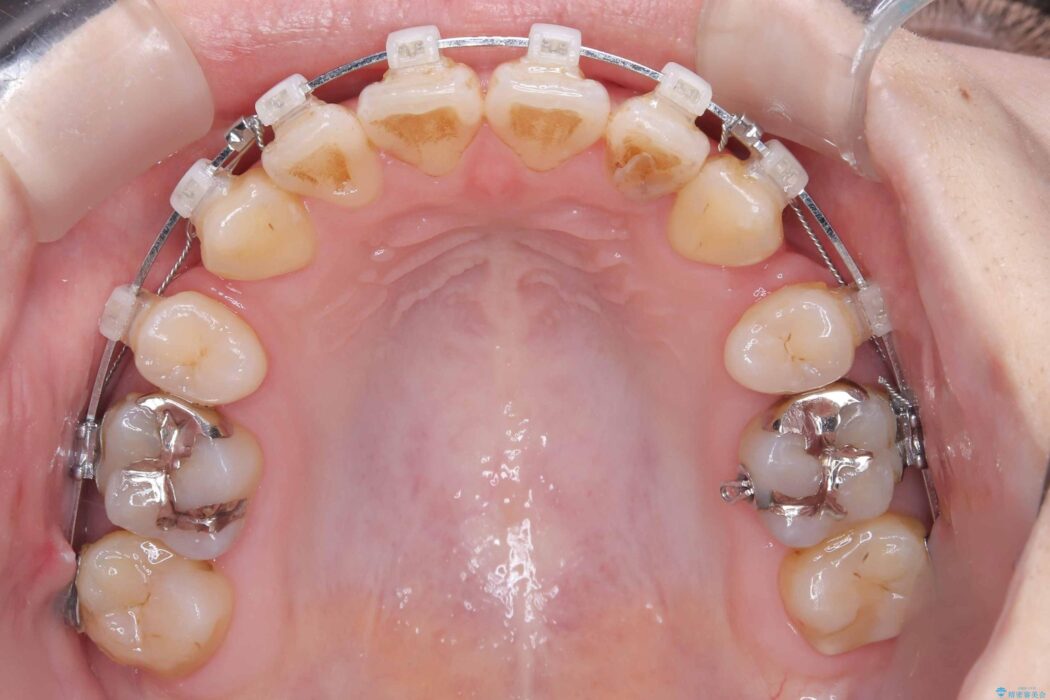

- 矯正装置:ワイヤー矯正(クリア装置)

精密検査の結果、上顎左右4番および下顎左右5番の計4本を抜歯し、目立ちにくいクリア装置にて治療を行いました。

また、虫歯があったので、矯正開始前に虫歯治療を行っております。